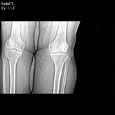

Синовиальная киста подколенной ямки. Синовиальная киста подколенной ямки OpenWindow.document.write("Medicus Amicus - Медицинские изображения")

Пациент R., 59 лет

Синовиальная киста подколенной ямки.

ЦКБ5 Южной железной дороги, отделение лучевой диагностики.

Протокол.

Контрастированы поверхностные и глубокие вены левого коленного сустава. Костно-деструктивные изменения не определяются. Дегенеративно-дистрофические изменения в проксимальном бежберцовом сочленении. В области подколенной ямки, прилежа медиально и кзади к подколенной мышце, полостное образование размерами 42х36х56 мм, содержащее жидкость (16-20 HU) с четкими ровными контурами, без признаков сдавления глубоких вен подколенной ямки.